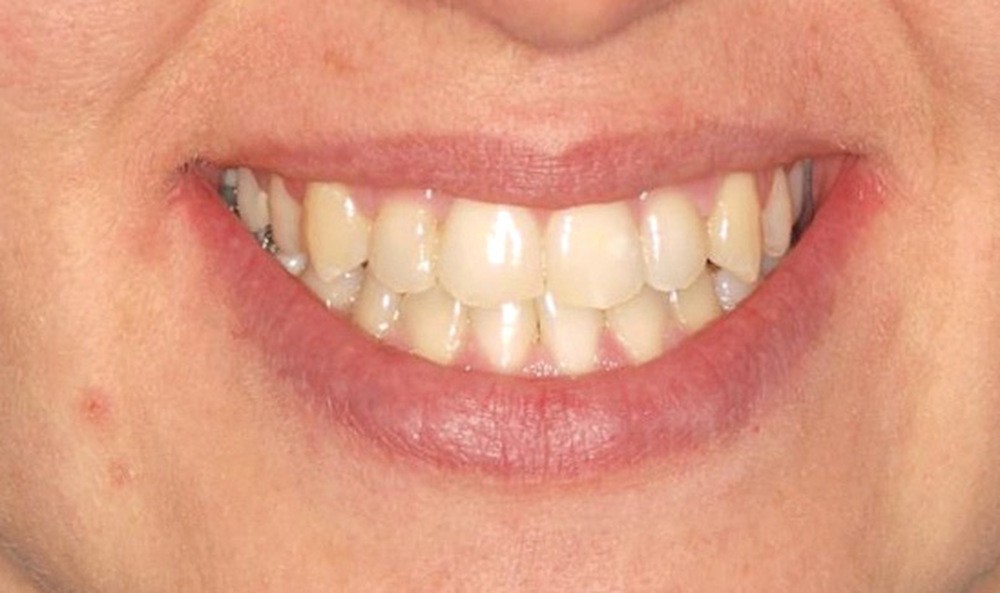

Le sourire est étroit, dégradé par les malpositions dentaires.

- Septième rendez-vous : les appareils sont déposés. Une empreinte numérique est prise pour réaliser trois aligneurs afin de parfaire le résultat occlusal et esthétique (fig. 3a-h).